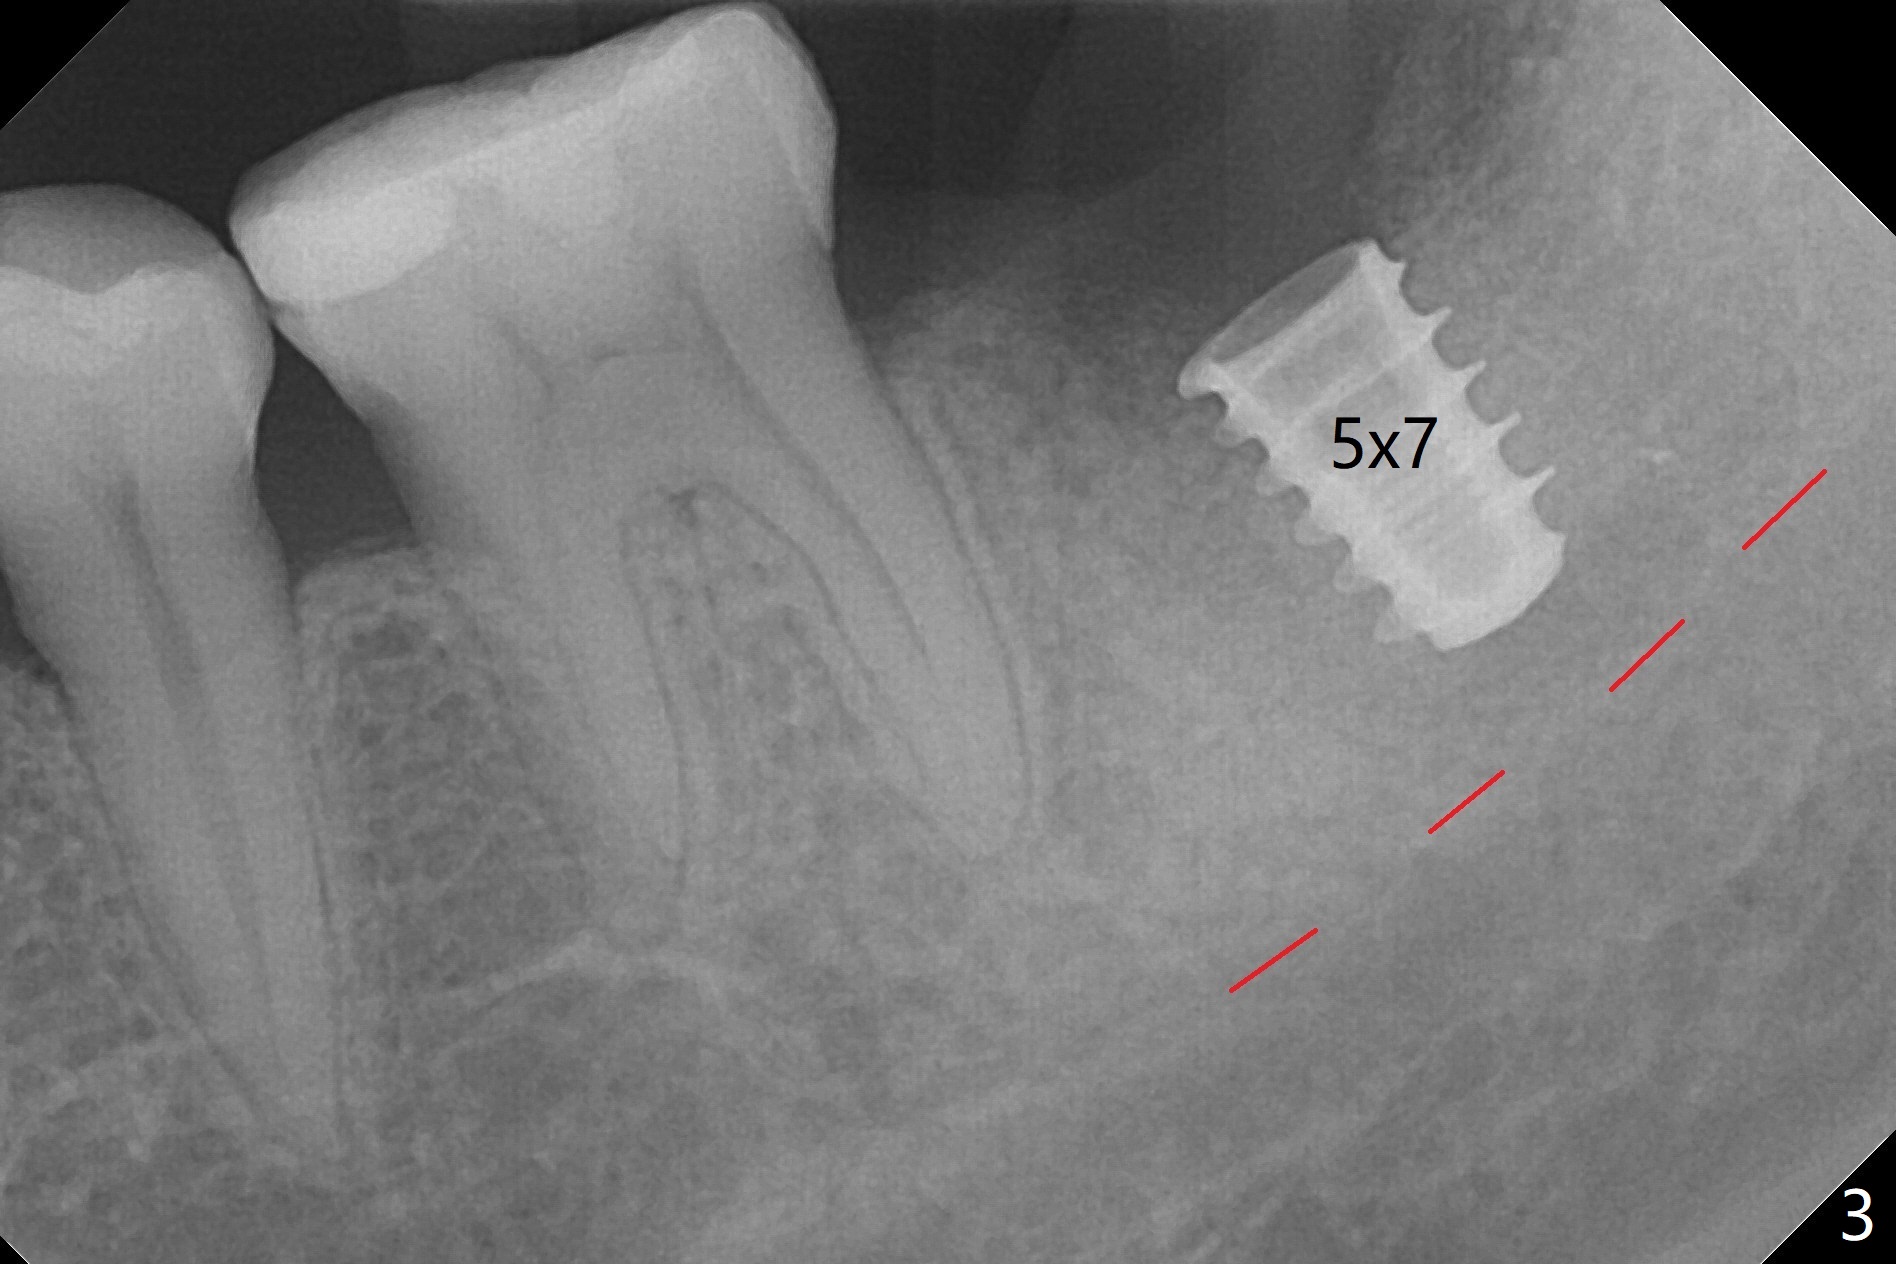

Six months post socket preservation at #18 (with moderate atrophy, Fig.1), a simplified surgical guide (Fig.2 with metal sleeve of 5 mm height and 2.93 mm diameter) determines initial osteotomy with 3.3 mm Magic Drill (MD), followed by 4.8 mm MD for 9 mm (gingival level) free hand. Since a 5x7 mm IBS implant is placed incompletely and in low stability (Fig.3 (in the graft bone)), a 4.3 mm MD is used for ~1 mm deeper. The implant is reseated to more satisfactory level (Fig.4: ~ 1 mm from the upper border of the Inferior Alveolar Canal (red dashed line)). The fearful patient is extremely pleased with quickness of the procedure as compared to that at #30 free hand. The wound heals normally 2 weeks postop. When she finishes the follow up appointment, she voluntarily talks to another patient who is hesitant about implant treatment. Impression is taken 5 months postop (Fig.5,6). There is no gap between the crown and abutment using abutcoping technique (Fig.7,8). The crown at #18 looks low probably related to long termed edentulism (Fig.9). The access hole is lingual (Fig.9), because the implant was placed lingual (Fig.10) due to use of a partial guide (Fig.11).